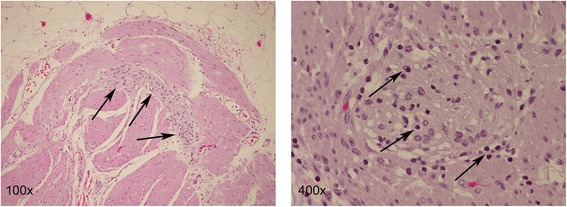

Figure 4.

H & E stains of resected sample of the small intestine. The myenteric plexi show an increased lymphoid infiltrate (100x, arrows), with a few plexi having a rather dense lymphoplasmacytic infiltrate (400x, arrows) consistent with myenteric ganglioneuritis. Magnification as indicated.

A 62-year-old gentleman with chronic obstructive pulmonary disease (COPD) from chronic smoking presented with worsening cough and constipation for three months. Within the last year, the patient was recurrently treated for COPD exacerbations without significant clinical improvement. The patient denied having had fever, pain, nausea, vomiting, night sweats, or weight loss. Vital signs were unremarkable and pertinent findings on physical exam included mild wheezes on both lungs with decreased breath sounds over the left upper lobe, enlarged left supraclavicular lymph nodes, and hypoactive bowel sounds. Laboratory exams revealed a low sodium concentration of 130 mEq/L (normal 136–145 mEq/L), however other results were all within normal range. Computed tomography (CT) and positron emission tomography (PET) scans showed a large left upper lobe fludeoxyglucose (FDG)-avid mass (standardized uptake value (SUV) 14.3) and enlarged left supraclavicular lymph nodes with avid FDG uptake (SUV 4.0) (Figures 1 and 2). Brain magnetic resonance imaging (MRI) revealed no metastatic disease in the brain. Subsequent fine-needle aspiration of the left supraclavicular mass and immunohistochemistry staining confirmed small cell neuroendocrine cancer positive for thyroid transcription factor (TTF-1) and synaptophysin confirming the diagnosis of small cell lung cancer (SCLC). The disease was determined as extensive disease due to the fact that tumor/nodal volume was too large to be encompassed in a tolerable radiation plan. During the hospital course, the patient’s bowel movements further declined despite an aggressive bowel regimen. Ultimately, the patient developed symptoms akin to bowel obstruction and a CT scan revealed small bowel distention with multiple air-fluid levels (Figure 3). Considering possible mechanical bowel obstruction surgery was consulted and the patient underwent small bowel resection of the terminal ileum and cecum. However, no tumorous obstruction was found and histologic examination of the resected sample revealed intense lymphoplasmacytic infiltration consistent with myenteric ganglioneuritis as this is typically found in CIPO (Figure 4). Anti-Hu antibodies were positive with a titer of 1:640. Collectively, the laboratory and pathologic findings were consistent with paraneoplastic CIPO with underlying SCLC.

CIPO is characterized by signs and symptoms of mechanical bowel obstruction in the absence of an anatomic lesion [12]. CIPO is idiopathic in most cases. Etiologies causing CIPO include neurologic, endocrine, collagen vascular, paraneoplastic, infectious and genetic disorders (Table 2) [12-14]. Histological features of CIPO include myenteric plexus infiltration with plasma cells and lymphocytes associated with axonal and neuronal degeneration [15,16]. Although paraneoplastic CIPO has been reported in connection with several solid tumors, SCLC and carcinoid tumors are by far the most common culprits [17,18]. Auto-antibodies such as anti-Hu that are frequently found to be positive in paraneoplastic, but not in non-paraneoplastic CIPO, often precede the overt manifestation of the underlying malignancy, rendering these antibodies to be potentially diagnostic and prognostic markers [2,19]. Anti-Hu antibodies are polyclonal complement-fixing immunoglobulins directed against nuclear proteins expressed in the neurons. A hypothesis is that these antibodies, together with the extensive lymphoplasmacytic infiltration, interact with the enteric plexus leading to its malfunction and, finally, to its irreversible damage resulting in un-correctable gut dysmotility [5,20,21]. To date, a relationship between anti-Hu antibody titers and severity of the clinical symptoms could not be demonstrated and convincing data indicating that a decrease in anti-Hu levels correlates with improved CIPO or better prognostic outcome are lacking [22-24]. In addition to CIPO, anti-Hu antibodies are also known to be involved in paraneoplastic CNS dysfunctions such as limbic encephalopathy and cerebellar degeneration as well as other paraneoplastic motor and autonomic neuropathies [20]. In general, anti-Hu antibodies associated with paraneoplastic neurologic conditions are called anti-Hu syndromes [20,25,26].